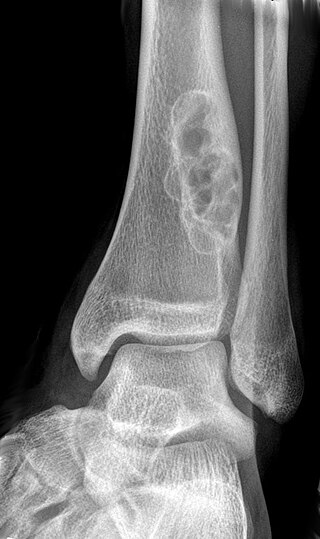

A bone tumor affected the elbow

Bone tumors are traditionally classified as noncancerous (benign) or cancerous (malignant).[4] Several features of bone tumors and soft tissue tumors overlap.[6] Their classification was revised by the World Health Organization (WHO) in 2020.[5] This newer classification divides bone tumors into tumors of cartilage, bone forming tumors, fibrogenic tumors, vascular tumors of bone, osteoclastic giant cell-rich tumors, notochordal tumors, other mesenchymal tumors of bone, and vascular tumors of bone.[1]